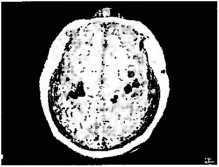

Рисунок 1.6

Магнитоэнцефалография (МЭГ): образ экспонируется на магнитно-резонансное отображение мозга пациента, у которого была ампутирована правая рука выше локтя.

Мозг рассматривается сверху. Правое полушарие показывает нормальную активацию корковых областей правой рухи (закрашено), лица (черная зона) и плеча (белая зона) в соответствии с картой Пенфилда. В левом полушарии нет активации, относящейся к правой отсутствующей рука, но теперь на згу область распространяется активность, идущая от лица и плеча

Чтобы напрямую проверить наши гипотезы «преобразования карты» и «перекреста проводов», мы использовали технику магнитоэнцефалографии, или МЭГ. Она показывает, какая часть мозга активируется при тактильном раздражении различных частей тела. Достаточно достоверно мы обнаружили, что у Виктора да и других пациентов с ампутированными конечностями) касание лица активирует не только область лица в мозгу, но также район руки в соответствии с картой Пенфилда (см. рис. 1.6). Это сильно отличается от картины, которую можно видеть у здорового мозга, — в данном случае касание лица активирует только лицевую область коры.